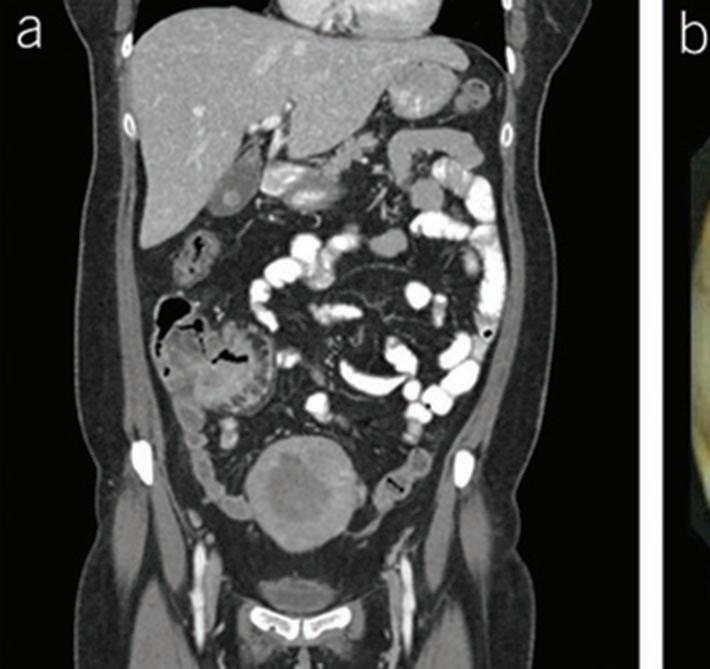

In a 1991 report in The American Journal of Gastroenterology, Drs. Alemayehu and Järnerot challenge prior orthodoxy that colonoscopy is contraindicated in patients with severe ulcerative colitis.